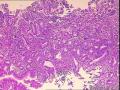

标本名称胃窦活检

大体所见灰白色小米粒大组织2点。

胃窦黏膜慢性炎

胃慢性炎

未见病变

胃窦粘膜慢性炎症伴部分腺体轻度不典型增生